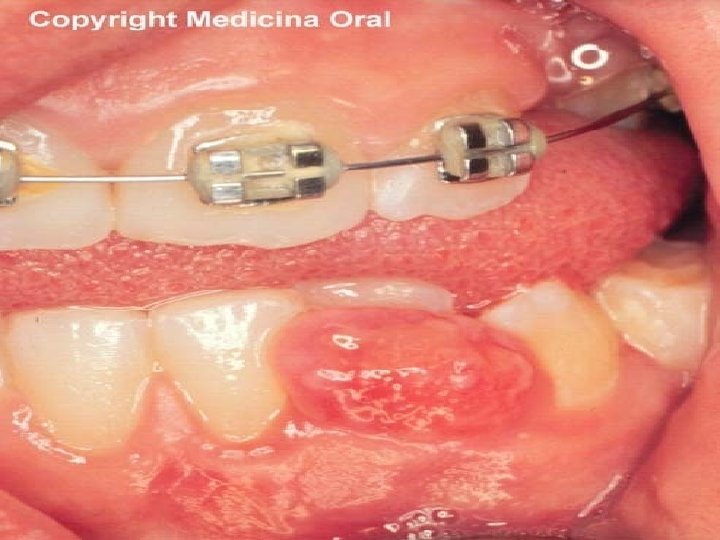

GRANULOMA PIOGENO CONCEPTO • Lesión nodular pseudotumoral secundaria a proliferación vascular reactiva ante diversos estímulos.

El granuloma piógeno suele presentarse como una lesión solitaria y asintomática. Se trata de un pequeño nódulo que raramente supera el centímetro de diámetro exofítico, en ocasiones pedunculado, de aspecto carnoso. Erosionado en superficies lisa Un dato clínico muy típico aunque no constante es la presencia de un collarete epidérmico

Características clínicas • Aumento de volumen pedunculado o sésil. • Consistencia blanda. • Entre rojo intenso, rojo oscuro o incluso violáceo. • Se puede presentar en cualquier parte de la mucosa bucal. • También se puede presentar en piel.

• Sangra con facilidad. • Generalmente se presenta en la encía. • De preferencia en mujeres y niños, pero se puede presentar en ambos sexos y cualquier edad. • Asintomatico aunque sangran con algun trauma • Recidivo

• Se destaca la apariencia multinodular de la lesion

• Granuloma piogeno. Tumoracion exofitica rodeada por un anillo hiperqueratosico